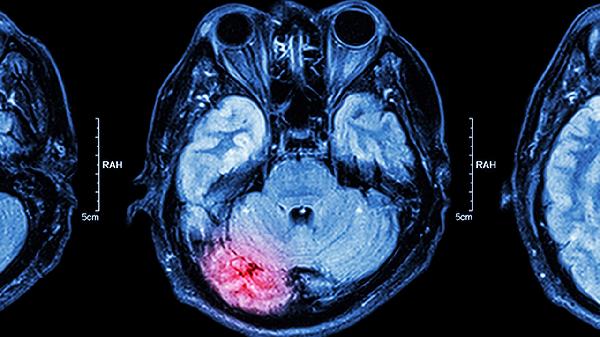

脑转移癌放疗后失眠怎么办

脑转移癌放疗后失眠是许多患者面临的常见问题,可能与放疗的副作用、心理压力或身体不适有关。失眠不仅影响生活质量,还可能延缓康复进程,需要及时调整和干预。